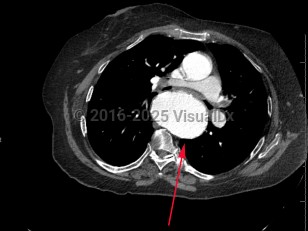

TAA is the dilatation of the artery compared to its original size; it is usually defined as the typical diameter of the artery increasing by 50%. A TAA will rarely manifest with symptoms, and about 95% of patients are asymptomatic. Catastrophic complications of TAA include aortic dissection and rupture, which are medical emergencies with high mortality rates. Most of these complications occur in the root or ascending aorta, followed by the descending aorta and aortic arch, respectively.

Biochemical and mechanical forces lead to TAA causing wall weakness and expansion. Changes in aortic wall compliance lead to increased stress on the artery and during systolic impulse can further exacerbate wall fragility, leading to aneurysms. Several factors that can lead to rupture or dissection include but are not limited to aortic ulcers (disrupted atherosclerotic plaques), intimal atherosclerosis, and intramural hematomas. Infectious aortitis can cause pseudoaneurysms (false aneurysms that occur at the site of arterial injury from infection or trauma).

Management depends on the location, shape, and size of the aneurysm, as well as symptoms and concomitant cardiovascular disease. In asymptomatic patients, management may consist of blood pressure control, specifically with beta blockers for impulse control, surveillance, and patient education to watch for early signs and symptoms of complications. Following complete evaluation and risk assessment, surgical repair or replacement may be undertaken. Less than half of patients who have a ruptured TAA survive to the hospital. Mortality can be as high as 54% within 6 hours and 76% at 24 hours of rupture.